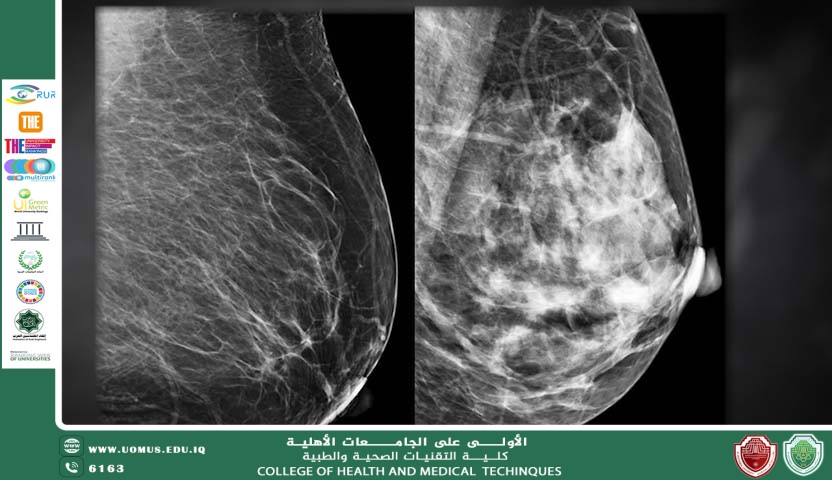

دور السونار في الكشف المبكر عن سرطان الثدي…مقالة للدكتورة الاختصاص هند خالد عبد

يُعد سرطان الثدي من أكثر أنواع السرطانات انتشارًا بين النساء عالميًا، ويشكل سببًا رئيسيًا للوفيات المرتبطة بالسرطان. إن الكشف المبكر يلعب دورًا حاسمًا في تحسين معدلات البقاء على قيد الحياة وزيادة فرص العلاج الناجح. ومن بين وسائل التشخيص المتاحة، يُعتبر فحص السونار (الموجات فوق الصوتية) أداة مهمة، خاصة عند استخدامه إلى جانب الماموجرام في برامج الكشف المبكر. مفهوم السونار وآلية عمله السونار هو تقنية تصوير طبي تعتمد على استخدام موجات صوتية عالية التردد لإنتاج صور تفصيلية للأنسجة الداخلية دون استخدام إشعاع مؤين. يتم وضع مسبار (Transducer) على جلد الثدي بعد تطبيق مادة هلامية لتسهيل انتقال الموجات الصوتية، وتنعكس هذه الموجات عن الأنسجة لتكوين صورة فورية على الشاشة. دور السونار في الكشف المبكر عن سرطان الثدي 1. مكمل أساسي للماموجرام السونار لا يُستخدم عادة كفحص أساسي منفرد، لكنه يُعد مكملًا مهمًا للماموجرام، خاصة لدى النساء ذوات الأنسجة الثديية الكثيفة، حيث قد تقل حساسية الأشعة السينية في اكتشاف الأورام الصغيرة. 2. التمييز بين الكتل الصلبة والكيسية يساعد السونار في التفريق بين: الكتل المملوءة بالسوائل (Cysts) غالبًا ما تكون حميدة. الكتل الصلبة التي قد تتطلب فحوصات إضافية مثل الخزعة. 3. تقييم الكتل غير الواضحة عند اكتشاف كتلة مشبوهة في الفحص السريري أو الماموجرام، يُستخدم السونار لتقييم طبيعتها وحدودها ومدى انتشارها. 4. توجيه الإجراءات التدخلية يُستخدم السونار لتوجيه الإبر أثناء أخذ الخزعة، مما يزيد من دقة الإجراء ويقلل المضاعفات. مزايا السونار آمن ولا يستخدم الإشعاع. غير مؤلم وسريع. مناسب للنساء الحوامل. فعال في تقييم الثدي الكثيف. محدوديات السونار يعتمد على مهارة وخبرة الفاحص. لا يُظهر التكلسات الدقيقة بوضوح مثل الماموجرام. قد يؤدي إلى نتائج إيجابية كاذبة تستدعي فحوصات إضافية. التقنيات الحديثة في سونار الثدي شهدت السنوات الأخيرة تطورًا في تقنيات السونار مثل: التصوير ثلاثي الأبعاد (3D Ultrasound) الإيلاستوغرافي (Elastography) الذي يقيس صلابة الأنسجة وهذه التقنيات حسّنت القدرة على التمييز بين الأورام الحميدة والخبيثة. الخلاصة يُعد السونار أداة فعالة ومهمة في الكشف المبكر عن سرطان الثدي، خاصة عند استخدامه بالتكامل مع وسائل التشخيص الأخرى. يساهم في تحسين دقة التشخيص وتقليل الحاجة إلى إجراءات غير ضرورية، مما يعزز فرص الاكتشاف المبكر والعلاج الناجح.